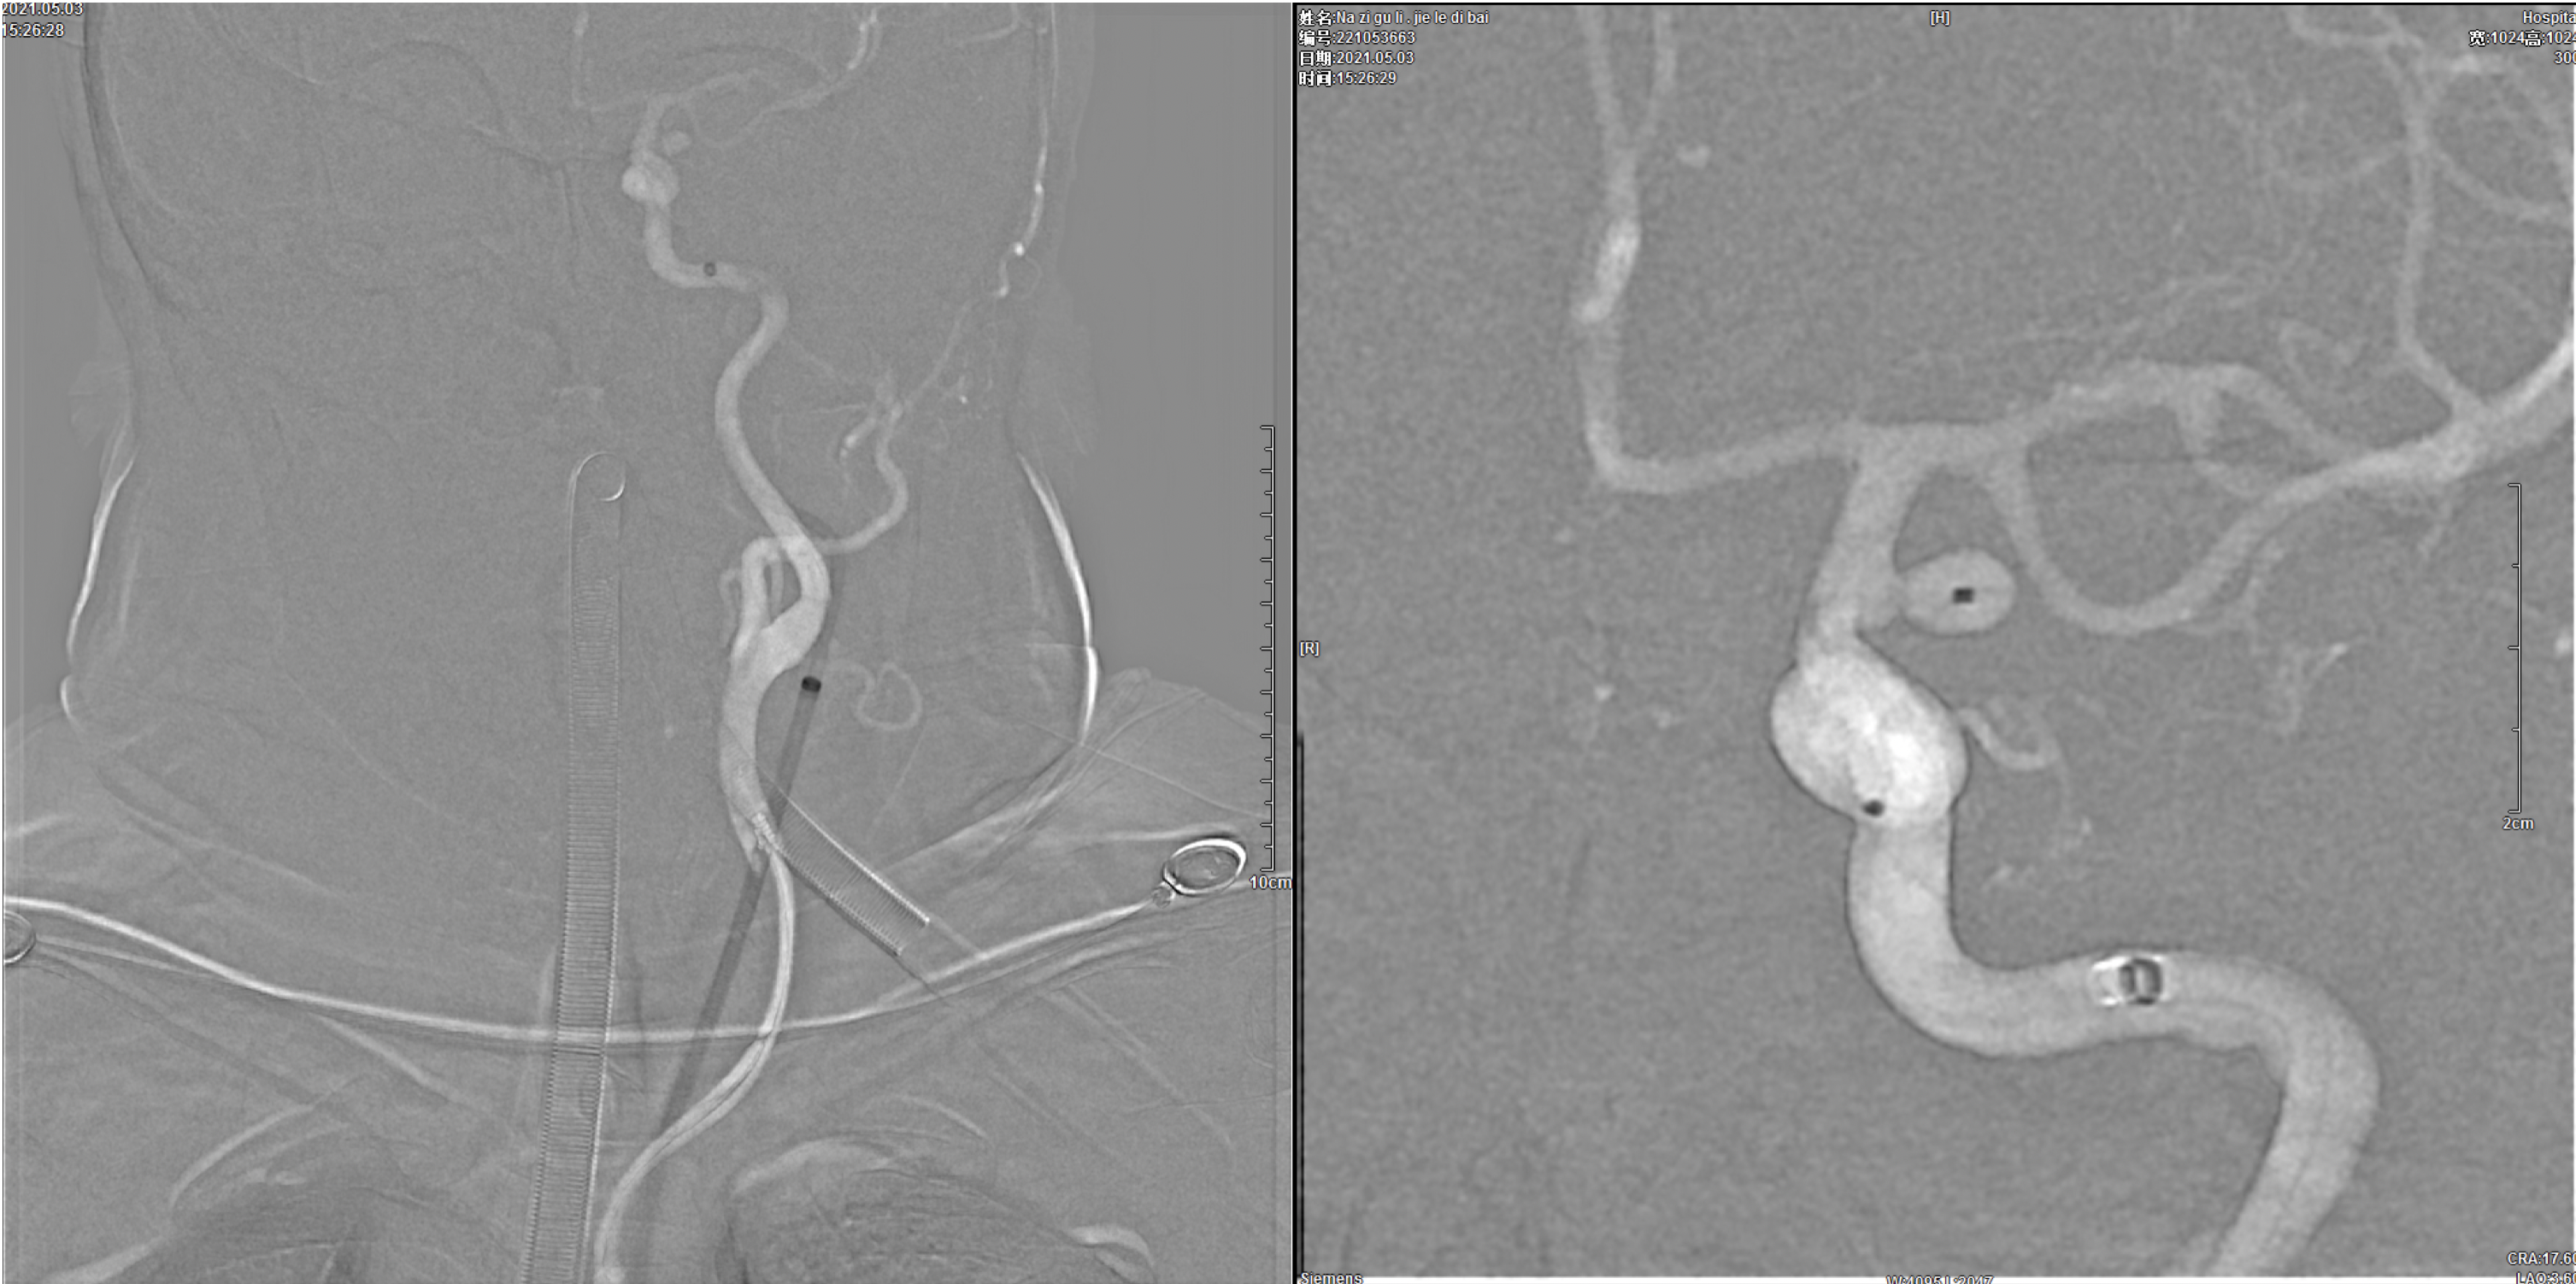

将7F长鞘+6F Navien再次超选至右侧颈内动脉建立通路系统后,Headway-21支架导管及Echelon-10栓塞微导管超选到位!

选择Lvis 3.5*20mm支架半释放辅助下先行后交通动脉瘤栓塞,动脉瘤栓塞满意后,撤除栓塞微导管。

将Echelon-10微导管超选入眼动脉段动脉瘤瘤腔内,行首枚弹簧圈栓塞。